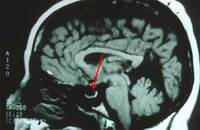

Magnetic resonance image (MRI) of empty sella on sagittal view

From the personal collection of Dr M. Wall; used with permission